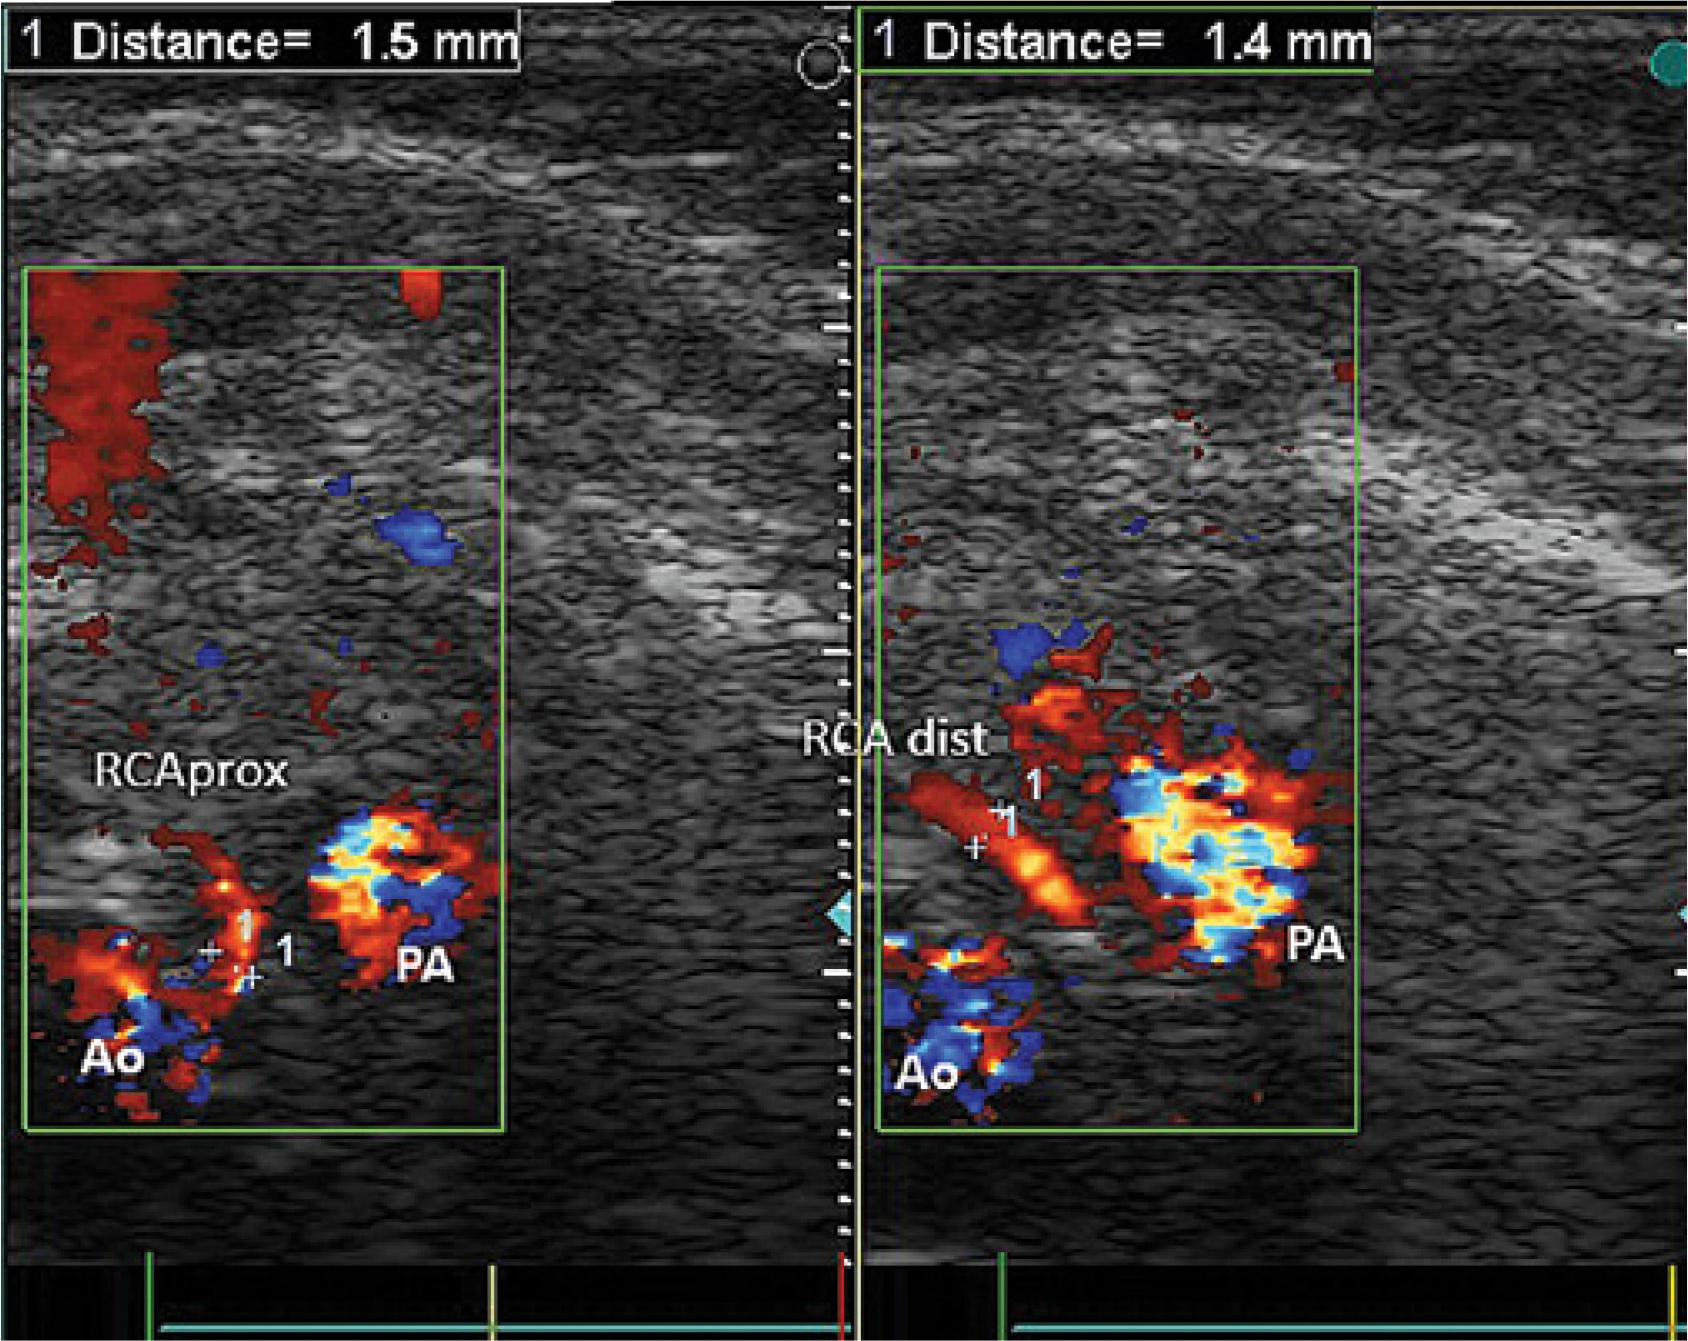

Fig. 1

Origin of the right coronary artery from the pulmonary artery visualized in ECHO 2D, in modified cross-sectional vascular parasternal projection. PA – pulmonary artery, Ao – cross-section of the initial segment of the ascending aorta, RCA – right coronary artery, LA – left atrium, RA – right atrium, Th – thymus, IAS – interatrial septum